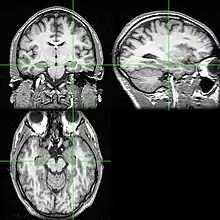

Neuroimágenes

Las pruebas de neuroimagen pueden identificar la causa de las crisis y el foco de las crisis, es decir, el lugar del cerebro donde comienzan las crisis.[5] En la epilepsia recién diagnosticada, la resonancia magnética (RM) puede detectar lesiones cerebrales en hasta el 12-14% de las personas con epilepsia.[31] Sin embargo, en las personas con epilepsia crónica, la RM puede detectar lesiones cerebrales en el 80% de las personas con epilepsia.[31] La RM de 3-Tesla se recomienda para aquellos con evidencia de epilepsia focal, como la epilepsia del lóbulo temporal.[5] Las anomalías identificadas mediante RM incluyen esclerosis hipocampal, displasia cortical focal, otras malformaciones cerebrales corticales del desarrollo, tumores del desarrollo y de bajo grado, hemangioma cavernoso, lesión cerebral hipóxico-isquémica, lesión cerebral traumática y encefalitis.[5]